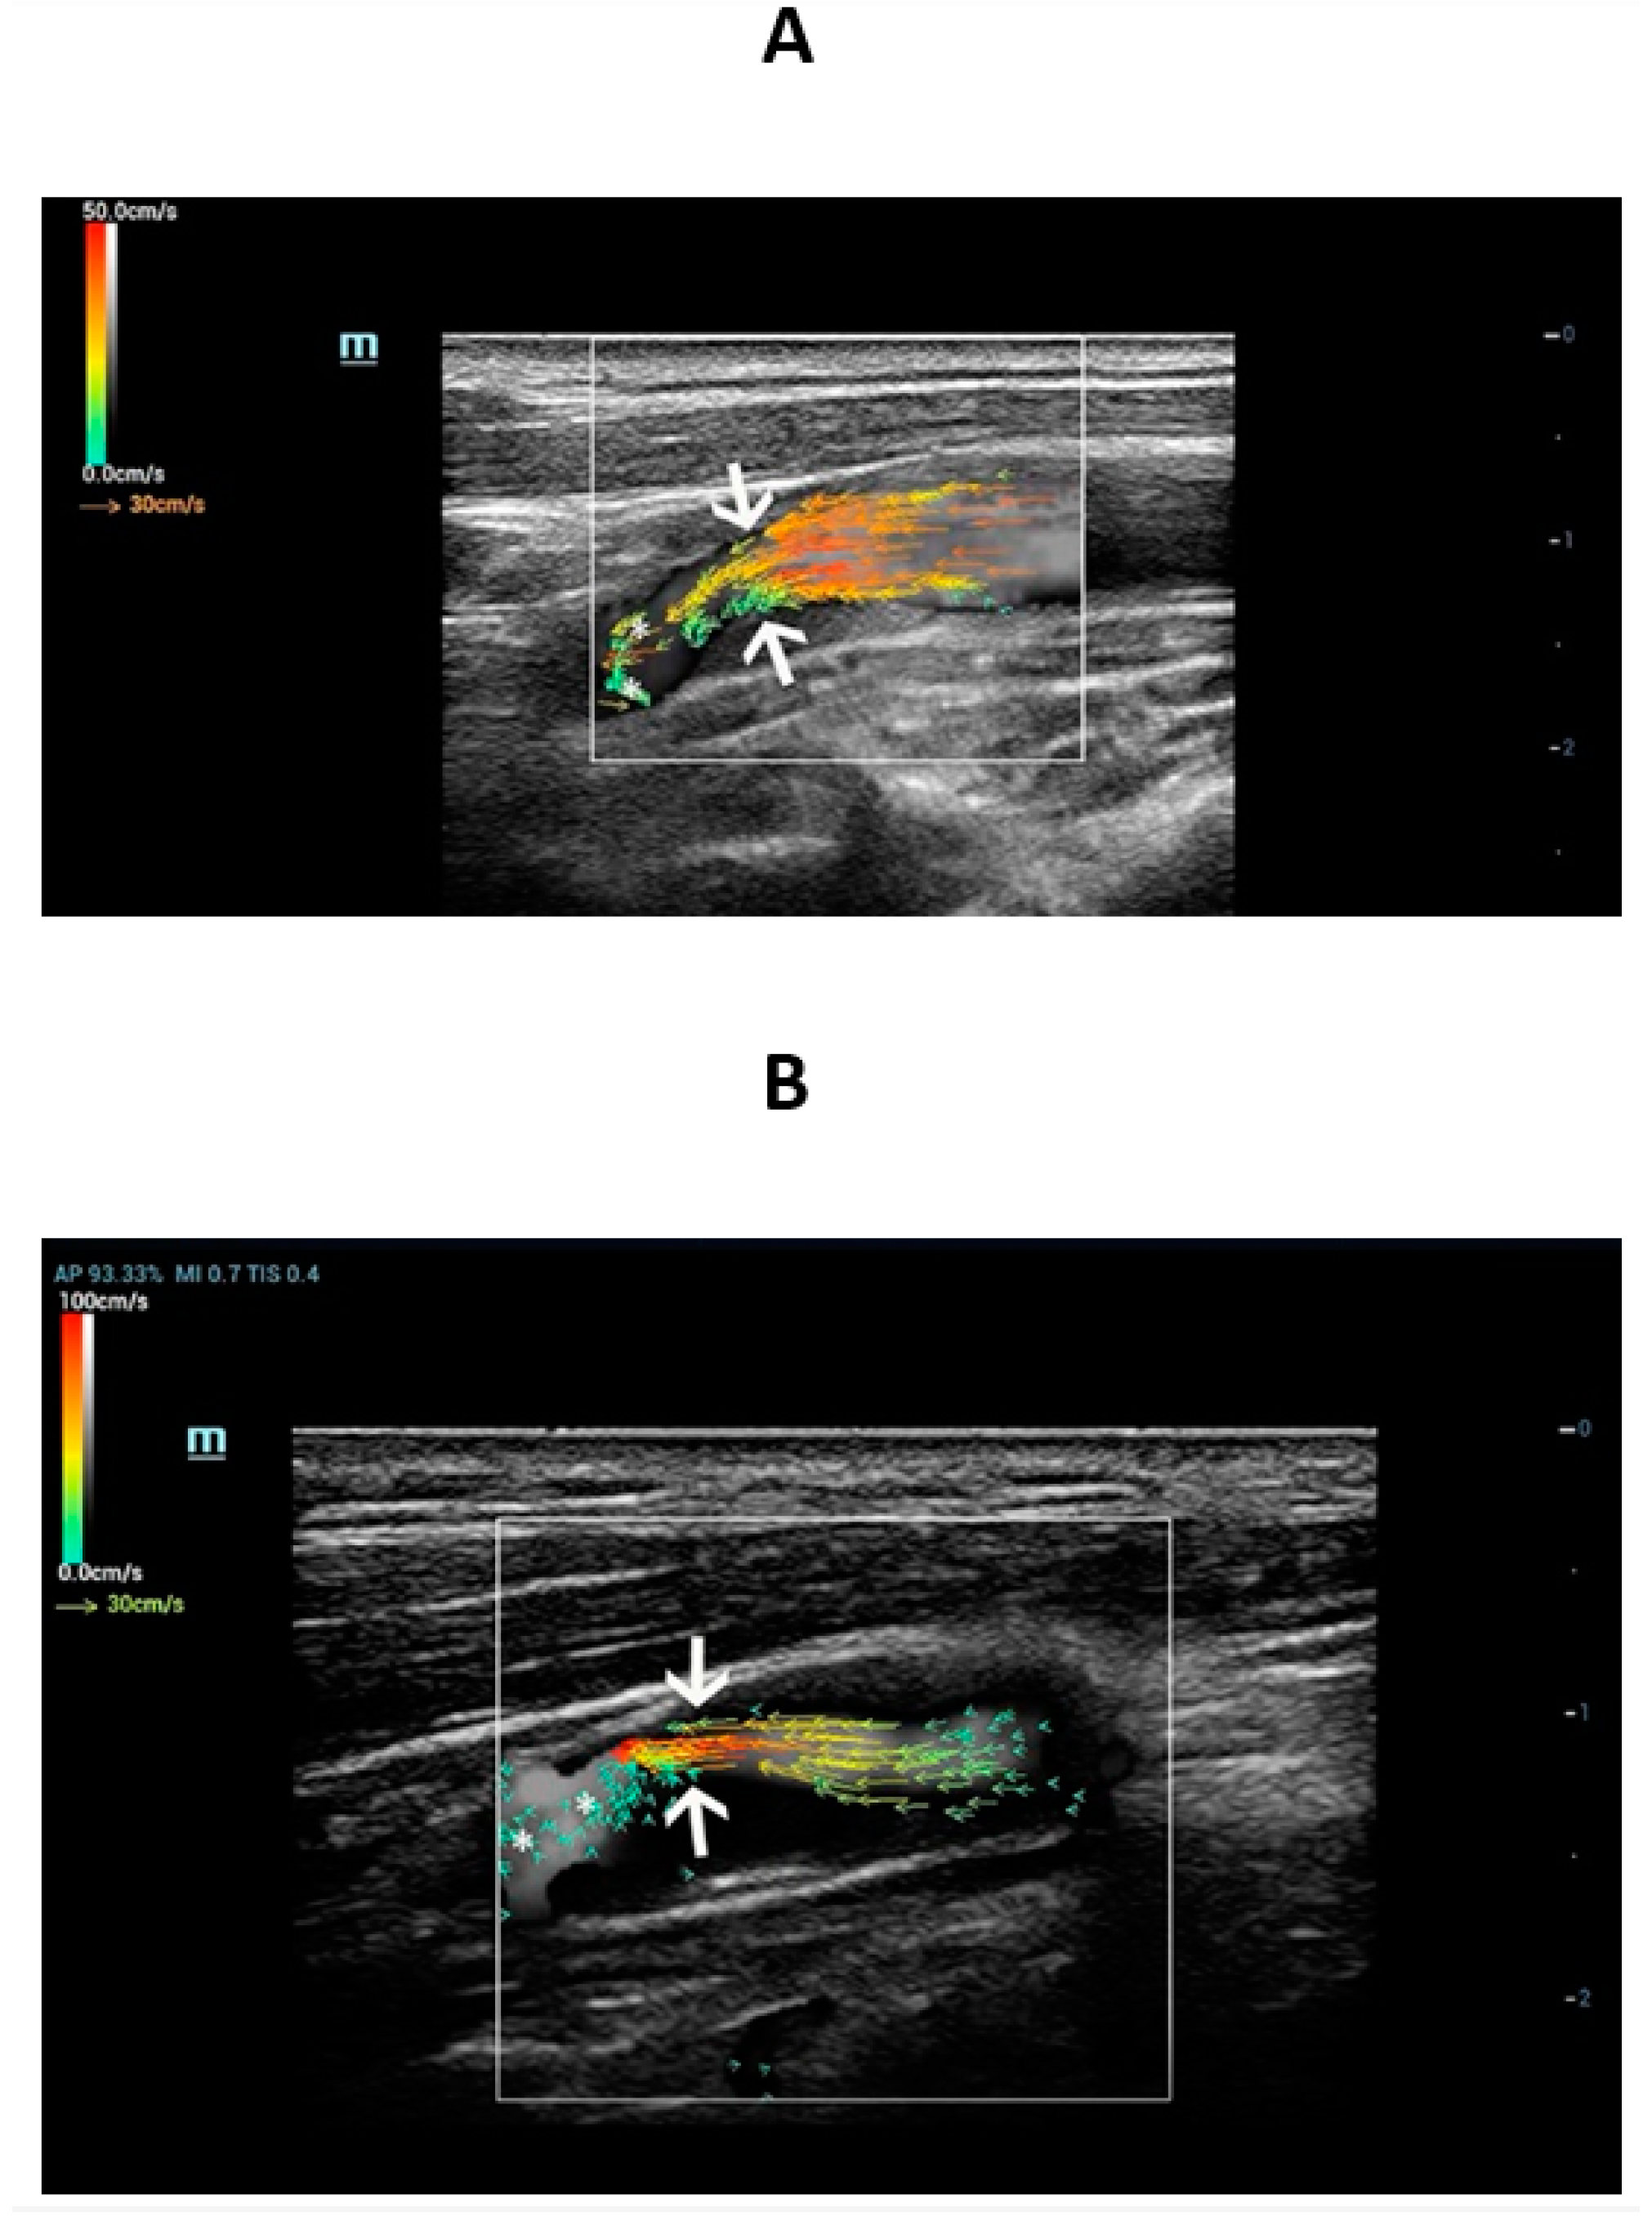

3.3. V Flow Imaging Features

- Qiu, Y.; Dong, Y.; Mao, F.; Zhang, Q.; Yang, D.; Chen, K.; Shi, S.; Zuo, D.; Tian, X.; Yu, L.; et al. High-Frame Rate Vector Flow Imaging Technique: Initial Application in Evaluating the Hemodynamic Changes of Carotid Stenosis Caused by Atherosclerosis. Front. Cardiovasc. Med. 2021, 8, 617391. [Google Scholar] [CrossRef]

- Qiu, Y.; Yang, D.; Zhang, Q.; Chen, K.; Dong, Y.; Wang, W.-P. V Flow technology in measurement of wall shear stress of common carotid arteries in healthy adults: Feasibility and normal values. Clin. Hemorheol. Microcirc. 2020, 74, 453–462. [Google Scholar] [CrossRef]